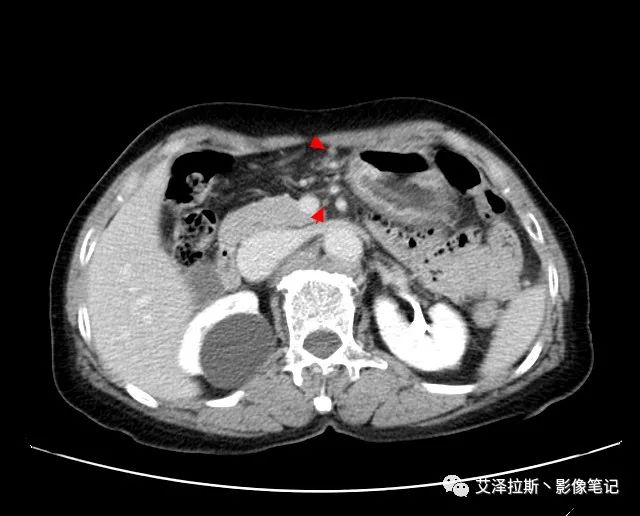

圖2 腫瘤

【影像所見】 胃竇部狹窄,胃壁環(huán)形增厚,小彎側(cè)見一巨大潰瘍,周圍伴“環(huán)堤征”,漿膜面不完整,胃周脂肪見網(wǎng)格狀條索影,病灶與肝臟左葉、胰腺鉤突脂肪間隙消失,增強(qiáng)掃描病灶明顯強(qiáng)化。引流區(qū)內(nèi)約15個區(qū)域淋巴結(jié)受累。

【診斷意見】 胃竇部胃癌(T4N3期) 該病例腫塊突破漿膜層,與肝臟左葉、胰腺鉤突分界不清,脂肪界面消失,定為T4期; 受累及的淋巴結(jié)為15個區(qū)域,定為N3; 有無遠(yuǎn)處轉(zhuǎn)移尚不明確,所以M期暫時無法確定。